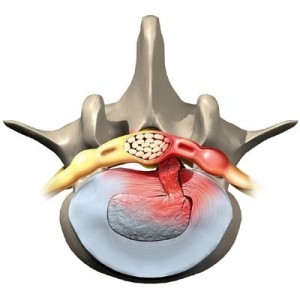

В основата на това заболяване е дегенерация на хрущяла междупрешленните дискове, които осигуряват гъвкавостта на гръбначния стълб.

Това може да доведе до по-пакет, деформацията диск на тялото и загуба на еластичност. Постепенно разработване, остеохондроза включва връзки, прешлени, и известна част от системата на кръвообращението, съседни на региона на локализация на патологичния процес.

Този тип се случва, когато ишиас остеохондроза поради лезии или възпаление на гръбначния нерв корени, които изместват междупрешленните дискове.

Ишиас е симптом комплекс показва наличието на въздействието на един от корените на гръбначния мозък.

Тя се причинява от притискане или прищипване корени на прешлените, между които са разположени.